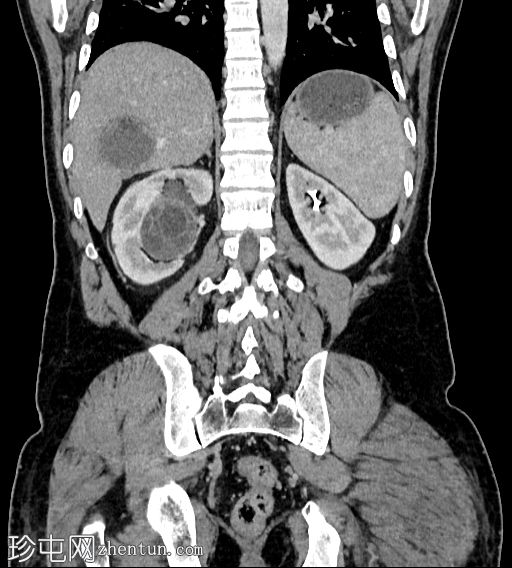

冠状位增强扫描(门静脉期)

肝脏VII段可见一边界清晰的囊性病变,内部有分隔,囊壁可见钙化。

右肾中央部分(肾门)可见一囊性病变,中心可见基质,周围可见子囊。该病变与肾盂肾盏无交通。病变周围可见两处高密度影,位于上、中肾盏,无法区分是结石还是病变壁钙化。另可见上极肾盏中度扩张。